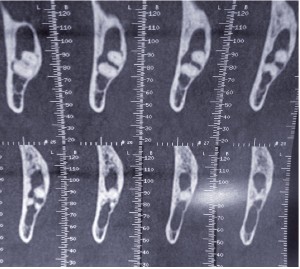

Le TDM retrouve une lésion lytique du ramus mandibulaire avec amincissement des corticales linguale et vestibulaire.

Une intervention chirurgicale à type d’exploration avec énucléation de la lésion et examen anatomopathologique est indiquée.